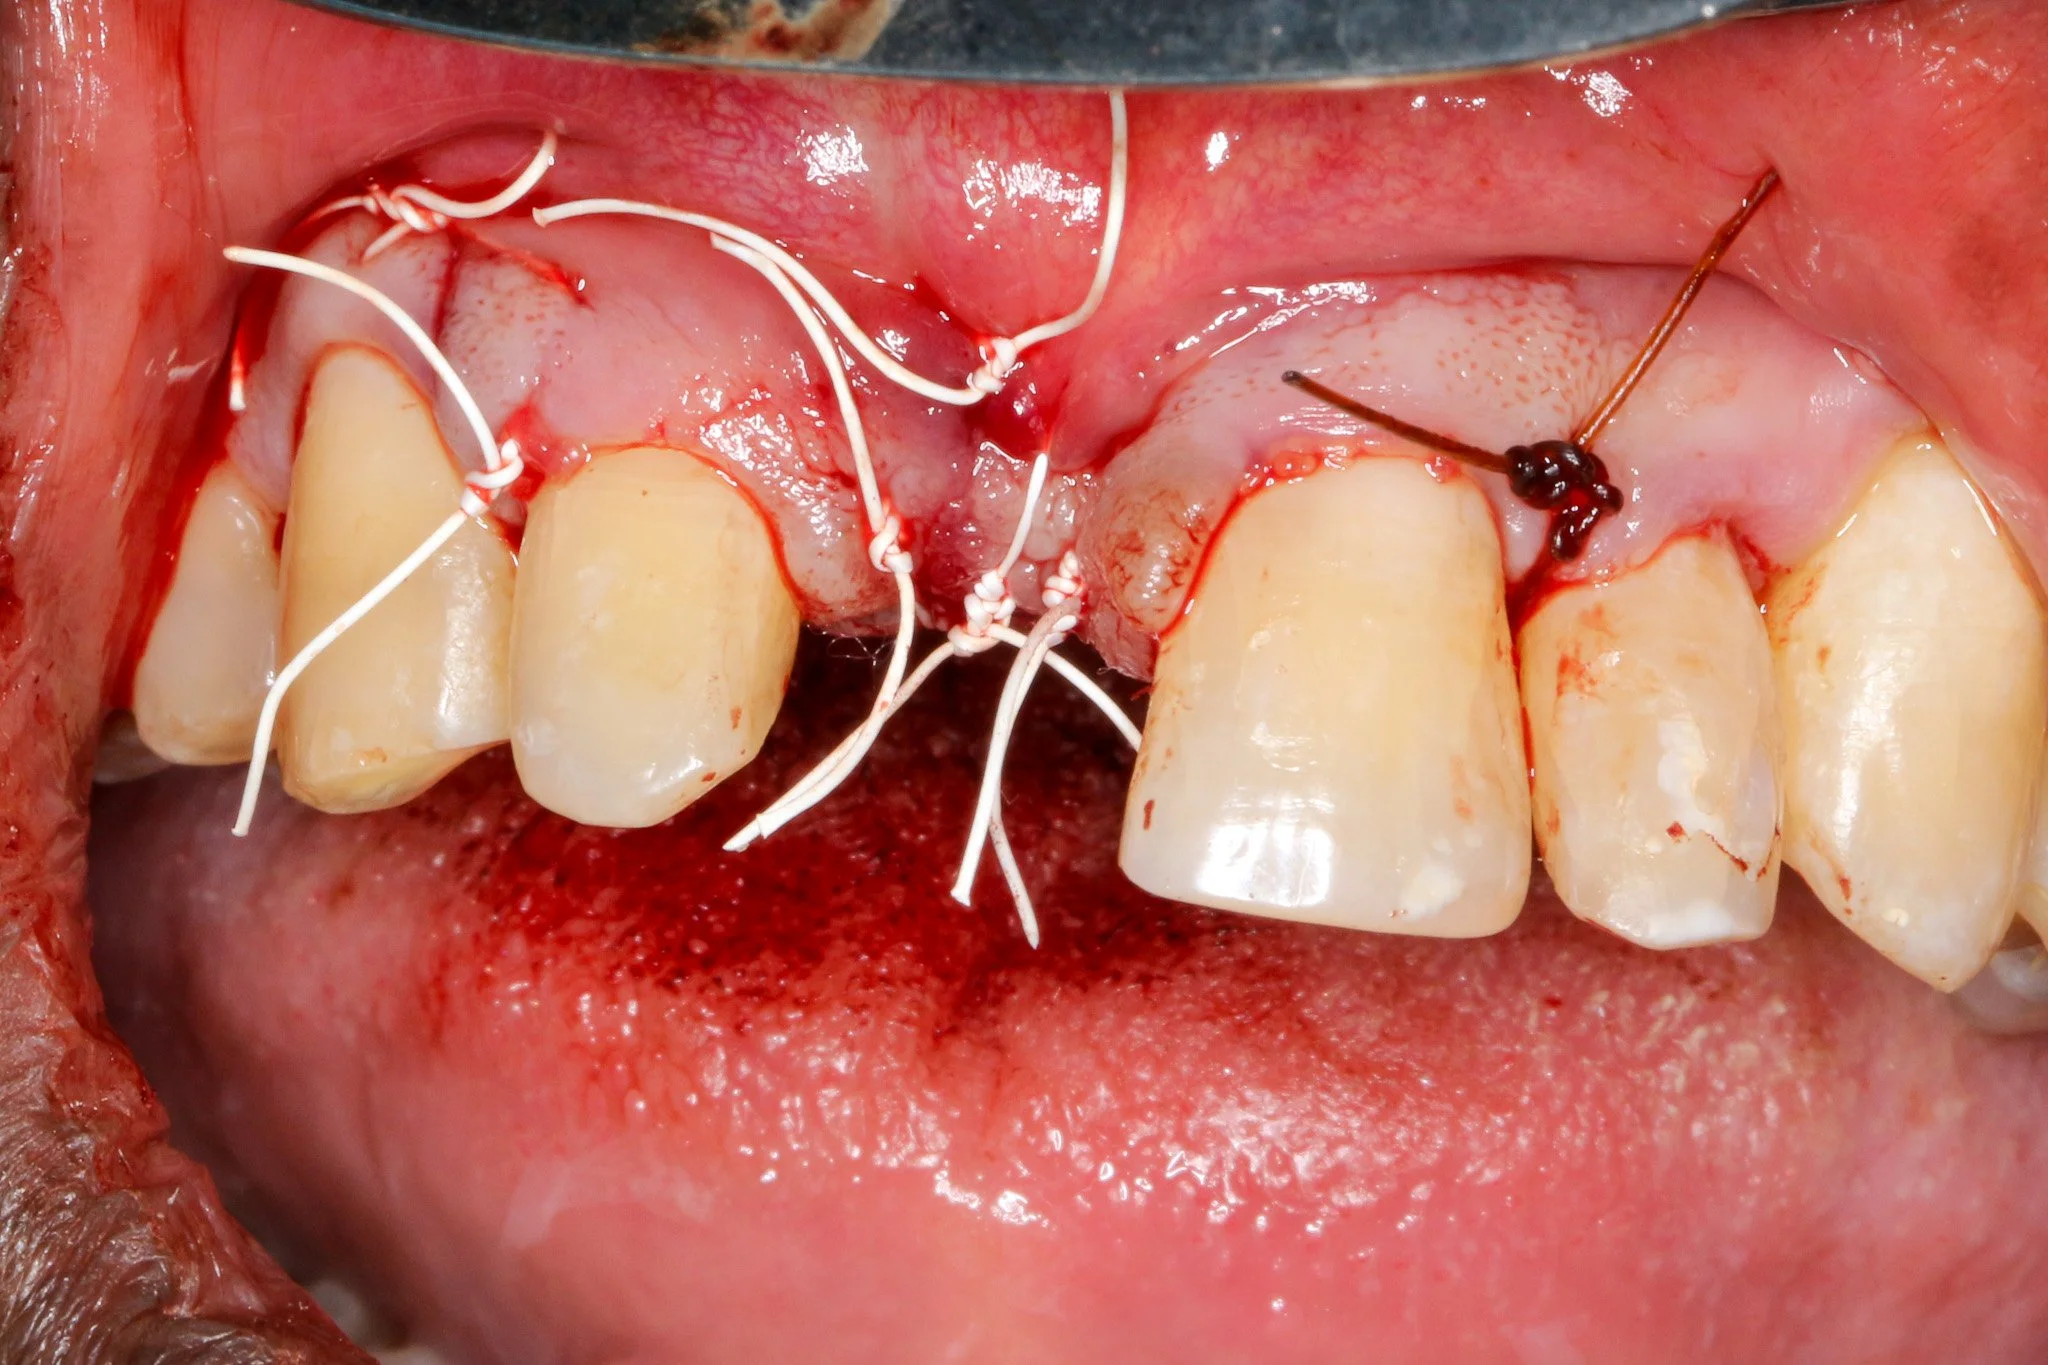

An ePTFE (polytetrafluoroethylene) suture was selected for its superior handling characteristics, minimal tissue reactivity, and reduced bacterial adhesion compared to conventional suture materials (Lilly et al., 2016). A double-layering suture technique combining horizontal mattress sutures with single interrupted sutures was implemented. Horizontal mattress sutures effectively evert wound edges and distribute tension away from the incision line (Burkhardt et al., 2008). Interrupted sutures ensure intimate tissue contact and optimal healing, which protects the underlying graft and membrane from bacterial infiltration. This sophisticated suturing approach has been shown to significantly reduce early wound dehiscence rates, particularly critical in GBR procedures where membrane exposure can compromise regenerative outcomes (Zucchelli et al., 2013).